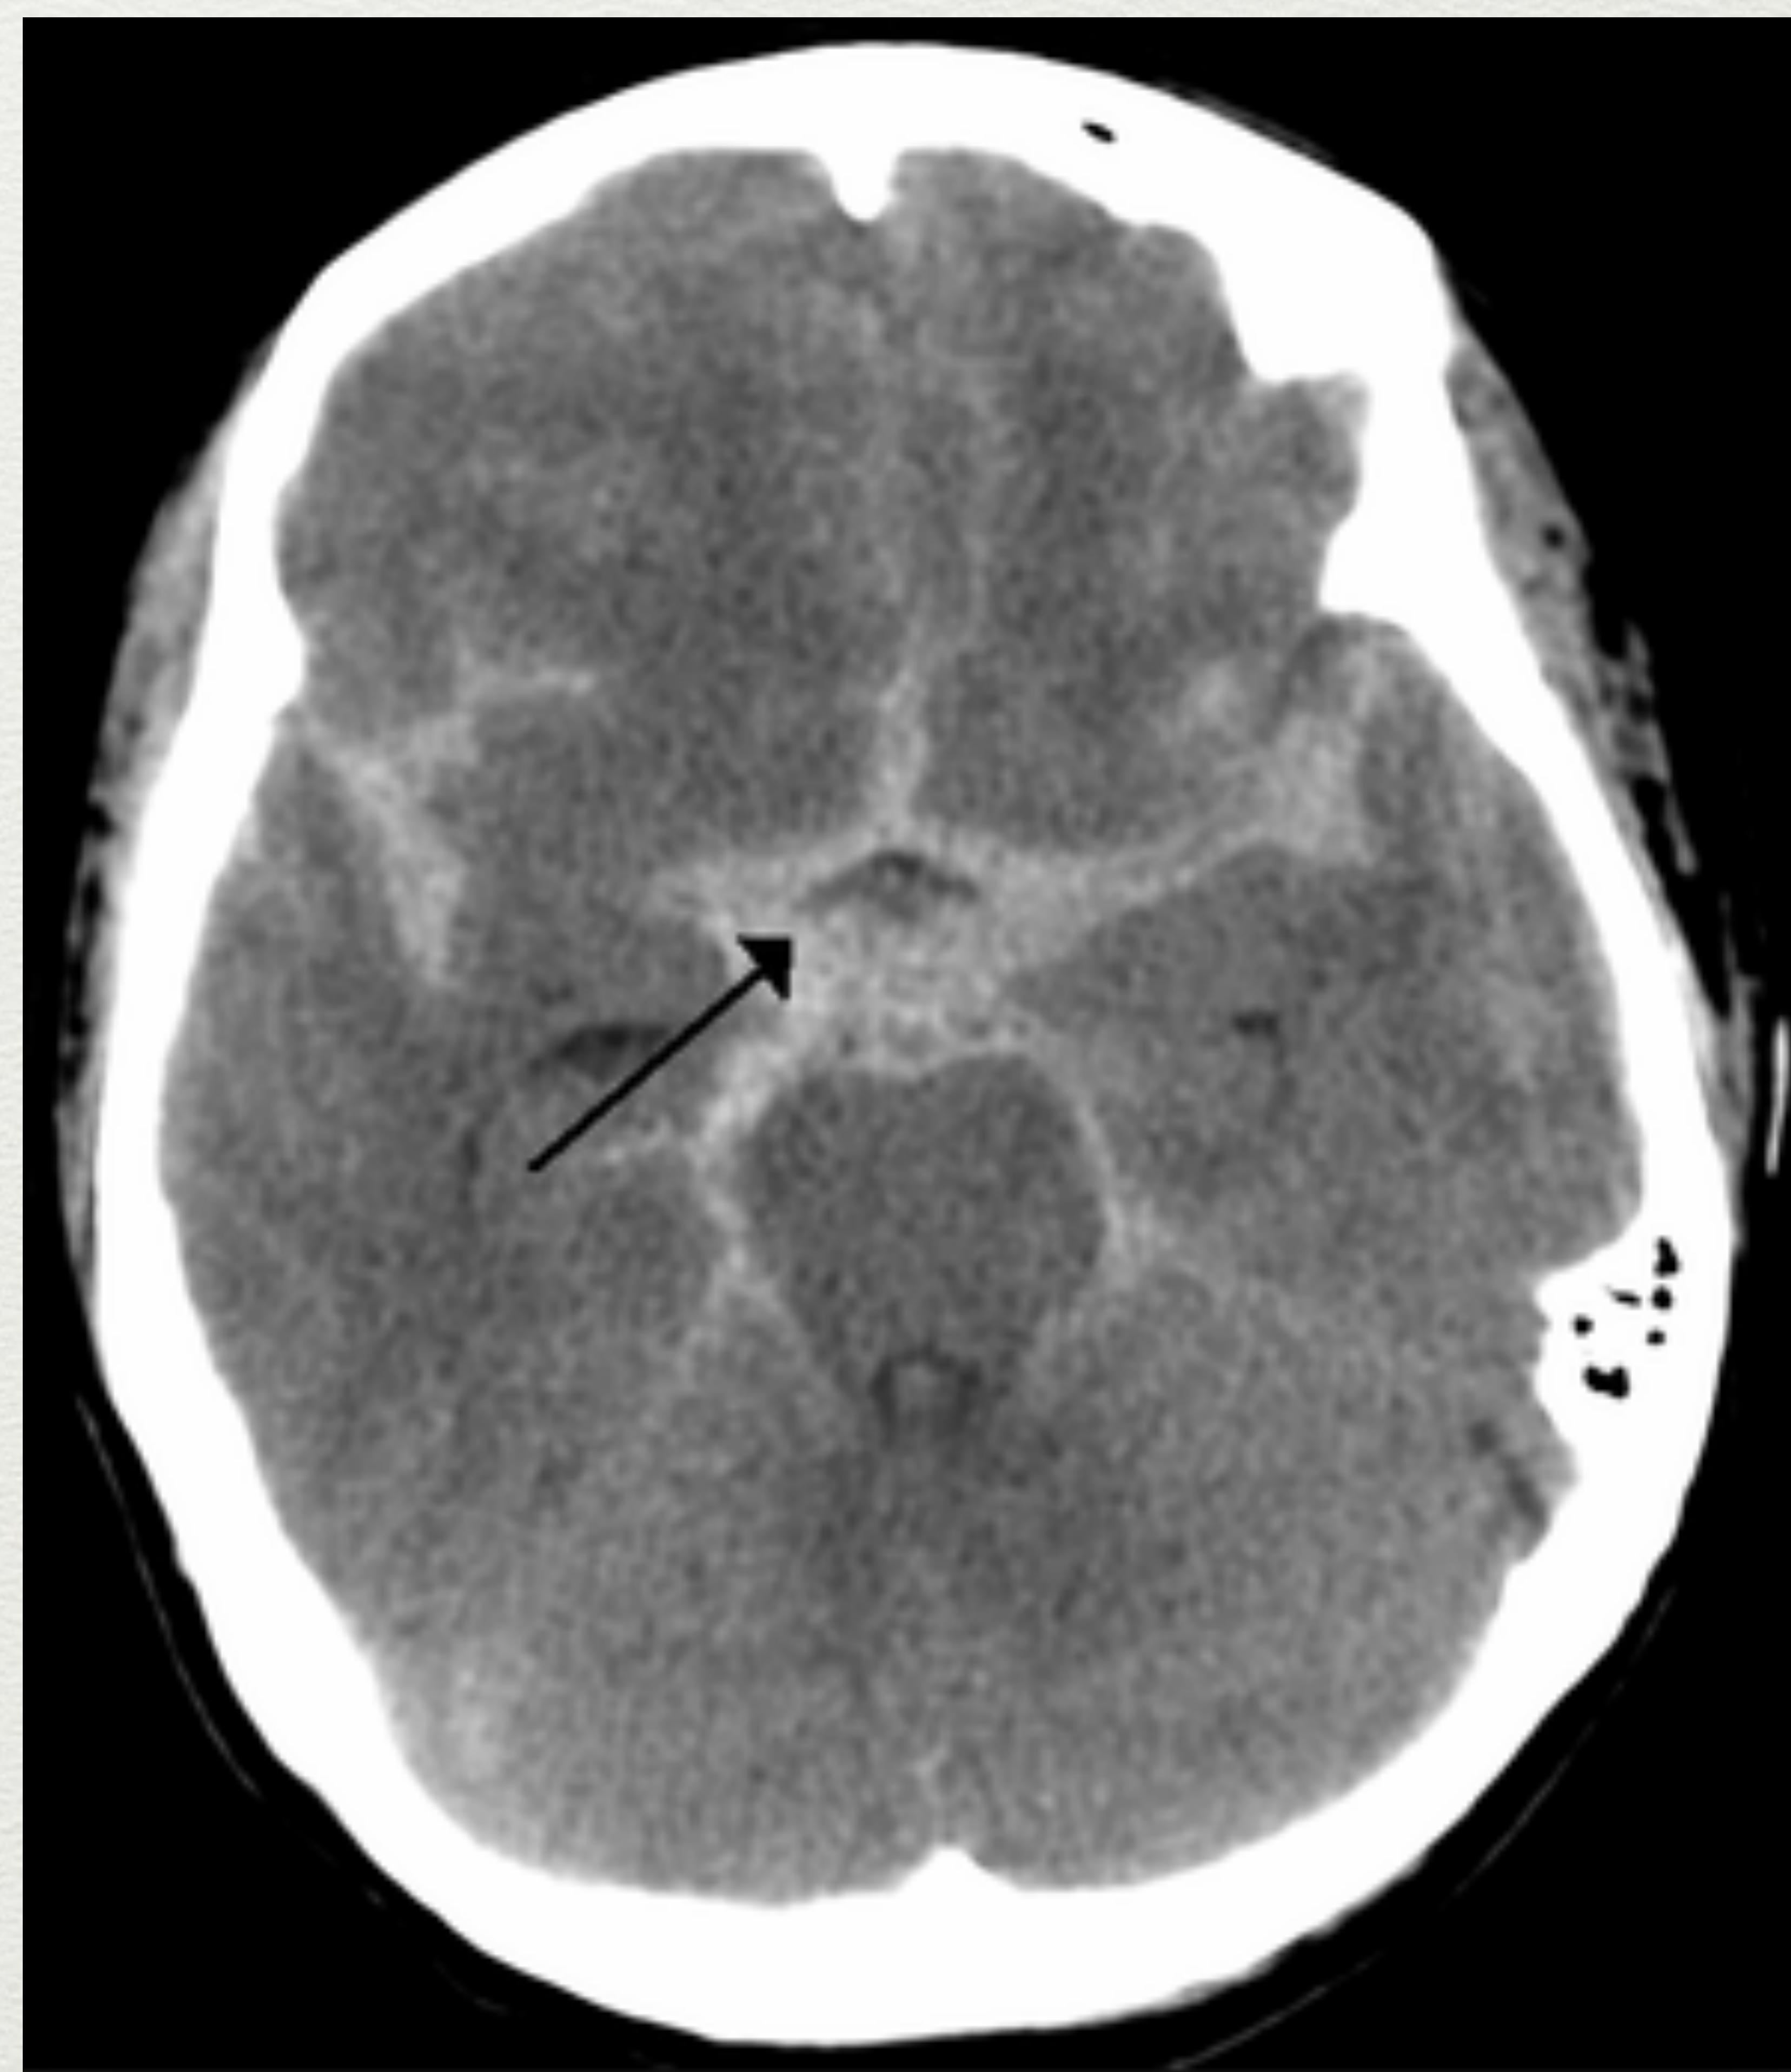

Subarachnoid Haematoma (SAH)

- Does not produce a haematoma or mass effect.

- May cause post-traumatic vasospasm.

- Appearance: Star sign.

- Management: Conservative treatment.

Axial CT scan showing subarachnoid haematoma (Star sign).